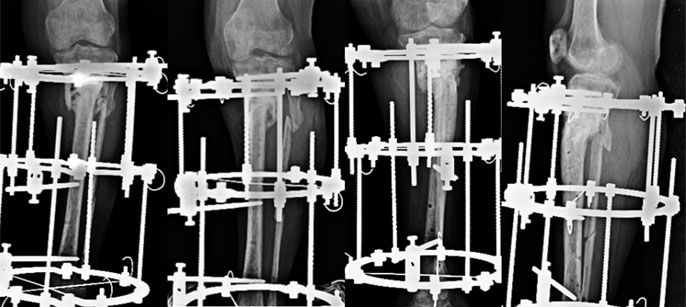

Nonunion - Proximal Tibia

| Pre Treatment |

This 41 year old lay presented to us in 2008 with nonunion of left proximal tibia since 2001. This was a pretty difficult situation for her as she was diagnosed as a case of Multiple Myeloma. She was operated for the tumor in the tibia and thereafter several times for controlling infection and getting the fracture to unite. She was barely able to walk with support and on top of that was very much depressed. |

| During Treatment |

We took up the challenge and an Ilizarov ring fixator was applied. Gradual compression at the fracture site was done and patient allowed to ambulate full weight bearing. |

| Post fixator removal |

The fracture healed and the fixator was removed but not before 16 months had passed from the surgery. Initially everything went well. Bone grafting was done after 6 months to increase the circumference of healing area. The fracture seemed to be on its way to heal but after about 4 months of bone grafting the proximal wires came loose and had to be reinserted. At the same time the fibula was cut in the middle third to allow collapse at the nonunion site. The fixator was removed after 16 months from the first surgery here. All this while she was walking with the fixator and was largely pain-free apart from occasional discomfort. She is now 8 months post removal and active and freely mobile. (See Testimonial Dr Gayatri Bhat) |